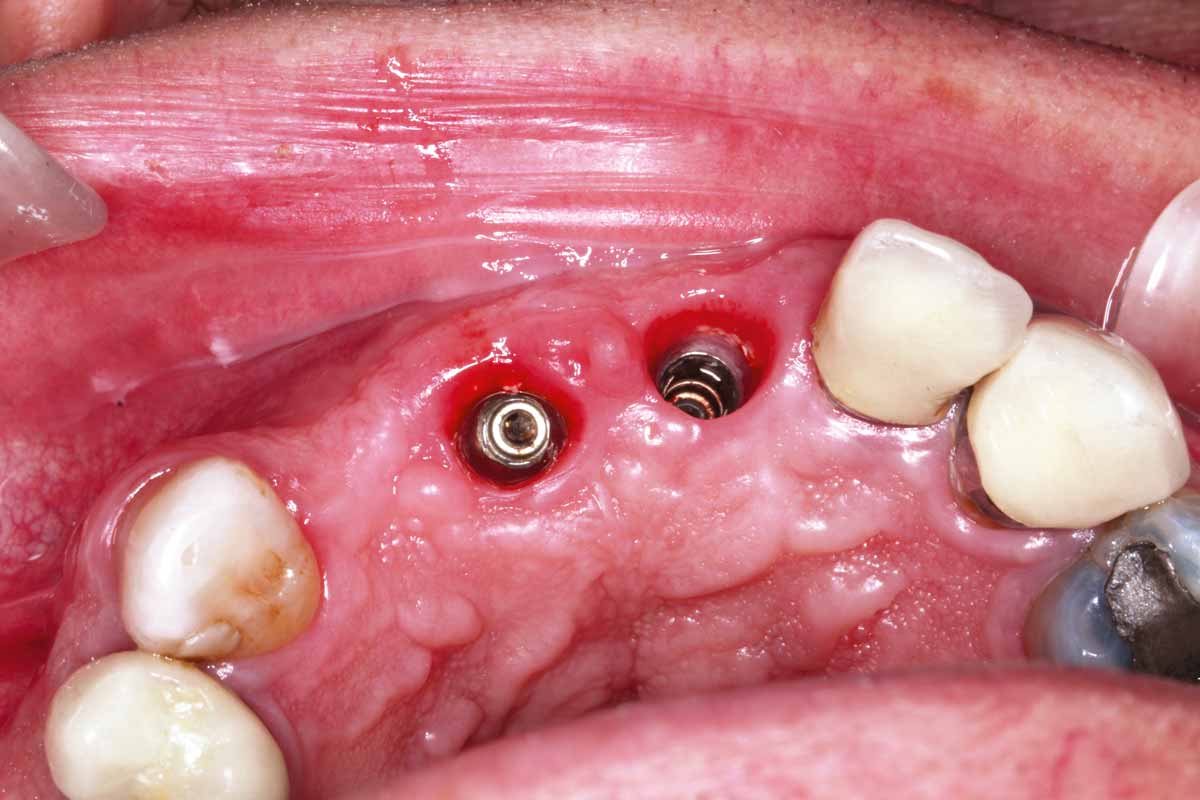

8/27 - Implants #11 and #21: occlusal view

GBR and soft tissue augmentation with cerabone® and mucoderm® - H. Maghaireh & V. Ivancheva